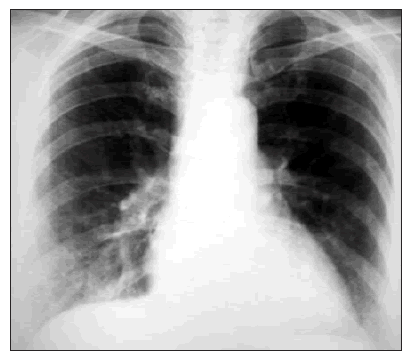

Данные объективного и дополнительных методов обследования. Состояние средней тяжести. Акроцианоз. Над легкими легочной звук с притуплением в нижних отделах. Аускультативно – жесткое дыхание, рассеянные полифонические хрипы, ослабление дыхания в задненижних отделах, там же – влажные мелкопузырчатые хрипы. Выделение при кашле небольшого количества слизисто-гнойной мокроты. В общеклиническом анализе крови лейкоцитоз (11,2), нейтрофильный сдвиг влево (п. – 11%, с. – 60%), ускоренное СОЭ – 14 мм/час. На рентгенограмме ОГК усиление легочного рисунка, негомогенная инфильтрация в нижних отделах. На спирограмме: ЖЭЛ – 70%, ОФВ1 – 34%.